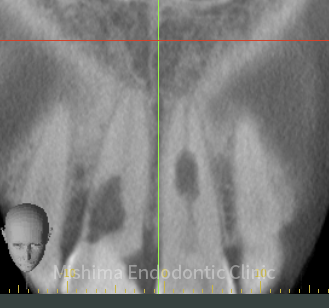

外部修復 バイオデンティン

パーフォレーションリペア バイオデンティン

パーフォレーション

| 治療内容 | 6年前にサバイバルゲームでBB弾が歯に当たり、歯が欠けた。 歯髄診査では、11,21ともにEPT+、Cold+。11は侵襲性歯頚部吸収、21は内部の炎症性吸収と診断。また、11にはパーフォレーションも認めた。 21は根管治療、ダイレクトボンディングにて対応。 11は、歯冠部の審美に対してはダイレクトボンディングにて対応。 まず侵襲性歯頚部吸収による吸収部を粘膜剥離しバイオデンティンにて外部より封鎖。後日、パーフォレーション部をバイオデンティンにて根管内部よりリペア。歯髄は正常と診断したが、予防的に根管治療を行うこととした。歯冠部からのアクセスが困難だったため、逆根管治療(歯根端切除術)にて対応。 |